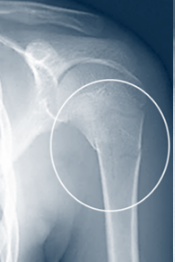

소아 골절은 통증이 있을 경우, 성인과 달리 성장판 손상이 발생했을 수 있어

반드시 소아정형외과 전문의를 찾아 성장판 손상 여부를 확인한 후 치료가 진행되어야 합니다.

성인 골절의 경우 X-ray만으로도 골절이 잘 드러나는 반면 소아 골절은 X-ray만으로 골절 여부를 판단하기 어려운 경우가 많습니다.

의사가 진찰을 하여 골절 가능성이 높다고 판단되면 골절 여부를 진단하기 위해 추가 검사를 진행하는 것 보다는 치료를 먼저 하는 역순으로 진행합니다.

보통 깁스 치료를 1-2주 한 후, X-ray를 촬영하면 뼈가 아무는 과정에서 골진이 나타나는데, 이때 소아 골절 여부를 정확히 진단할 수가 있습니다.

골절 형태 뿐만 아니라 소아를 치료할 때는 성장판 손상 여부를 자세히 살펴보아야 합니다.